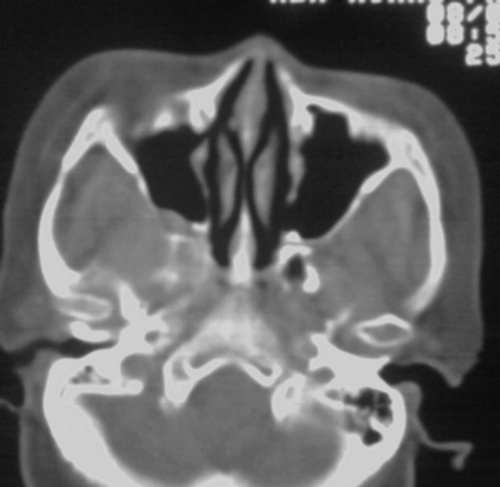

以下是引用随光逐影在2008-3-28 11:41:00的发言:[br]右侧蝶骨大翼骨质破坏,骨质破坏区内为软组织密度影填塞,右侧翼腭窝似有扩大,右侧乳突部分蜂房密度增高;疑鼻咽部肿瘤。建议:行鼻咽部ct扫描检查。另:右侧上颌窦黏膜下囊肿(或息肉)。

以下是引用jiangjing在2008-3-28 14:09:00的发言:[br]右侧蝶骨大翼骨质破坏,骨质破坏区内为软组织密度影填塞,右侧翼腭窝似有扩大,右侧乳突部分蜂房密度增高;疑鼻咽部肿瘤。建议:行鼻咽部ct扫描检查。另:右侧上颌窦黏膜下囊肿(或息肉)。